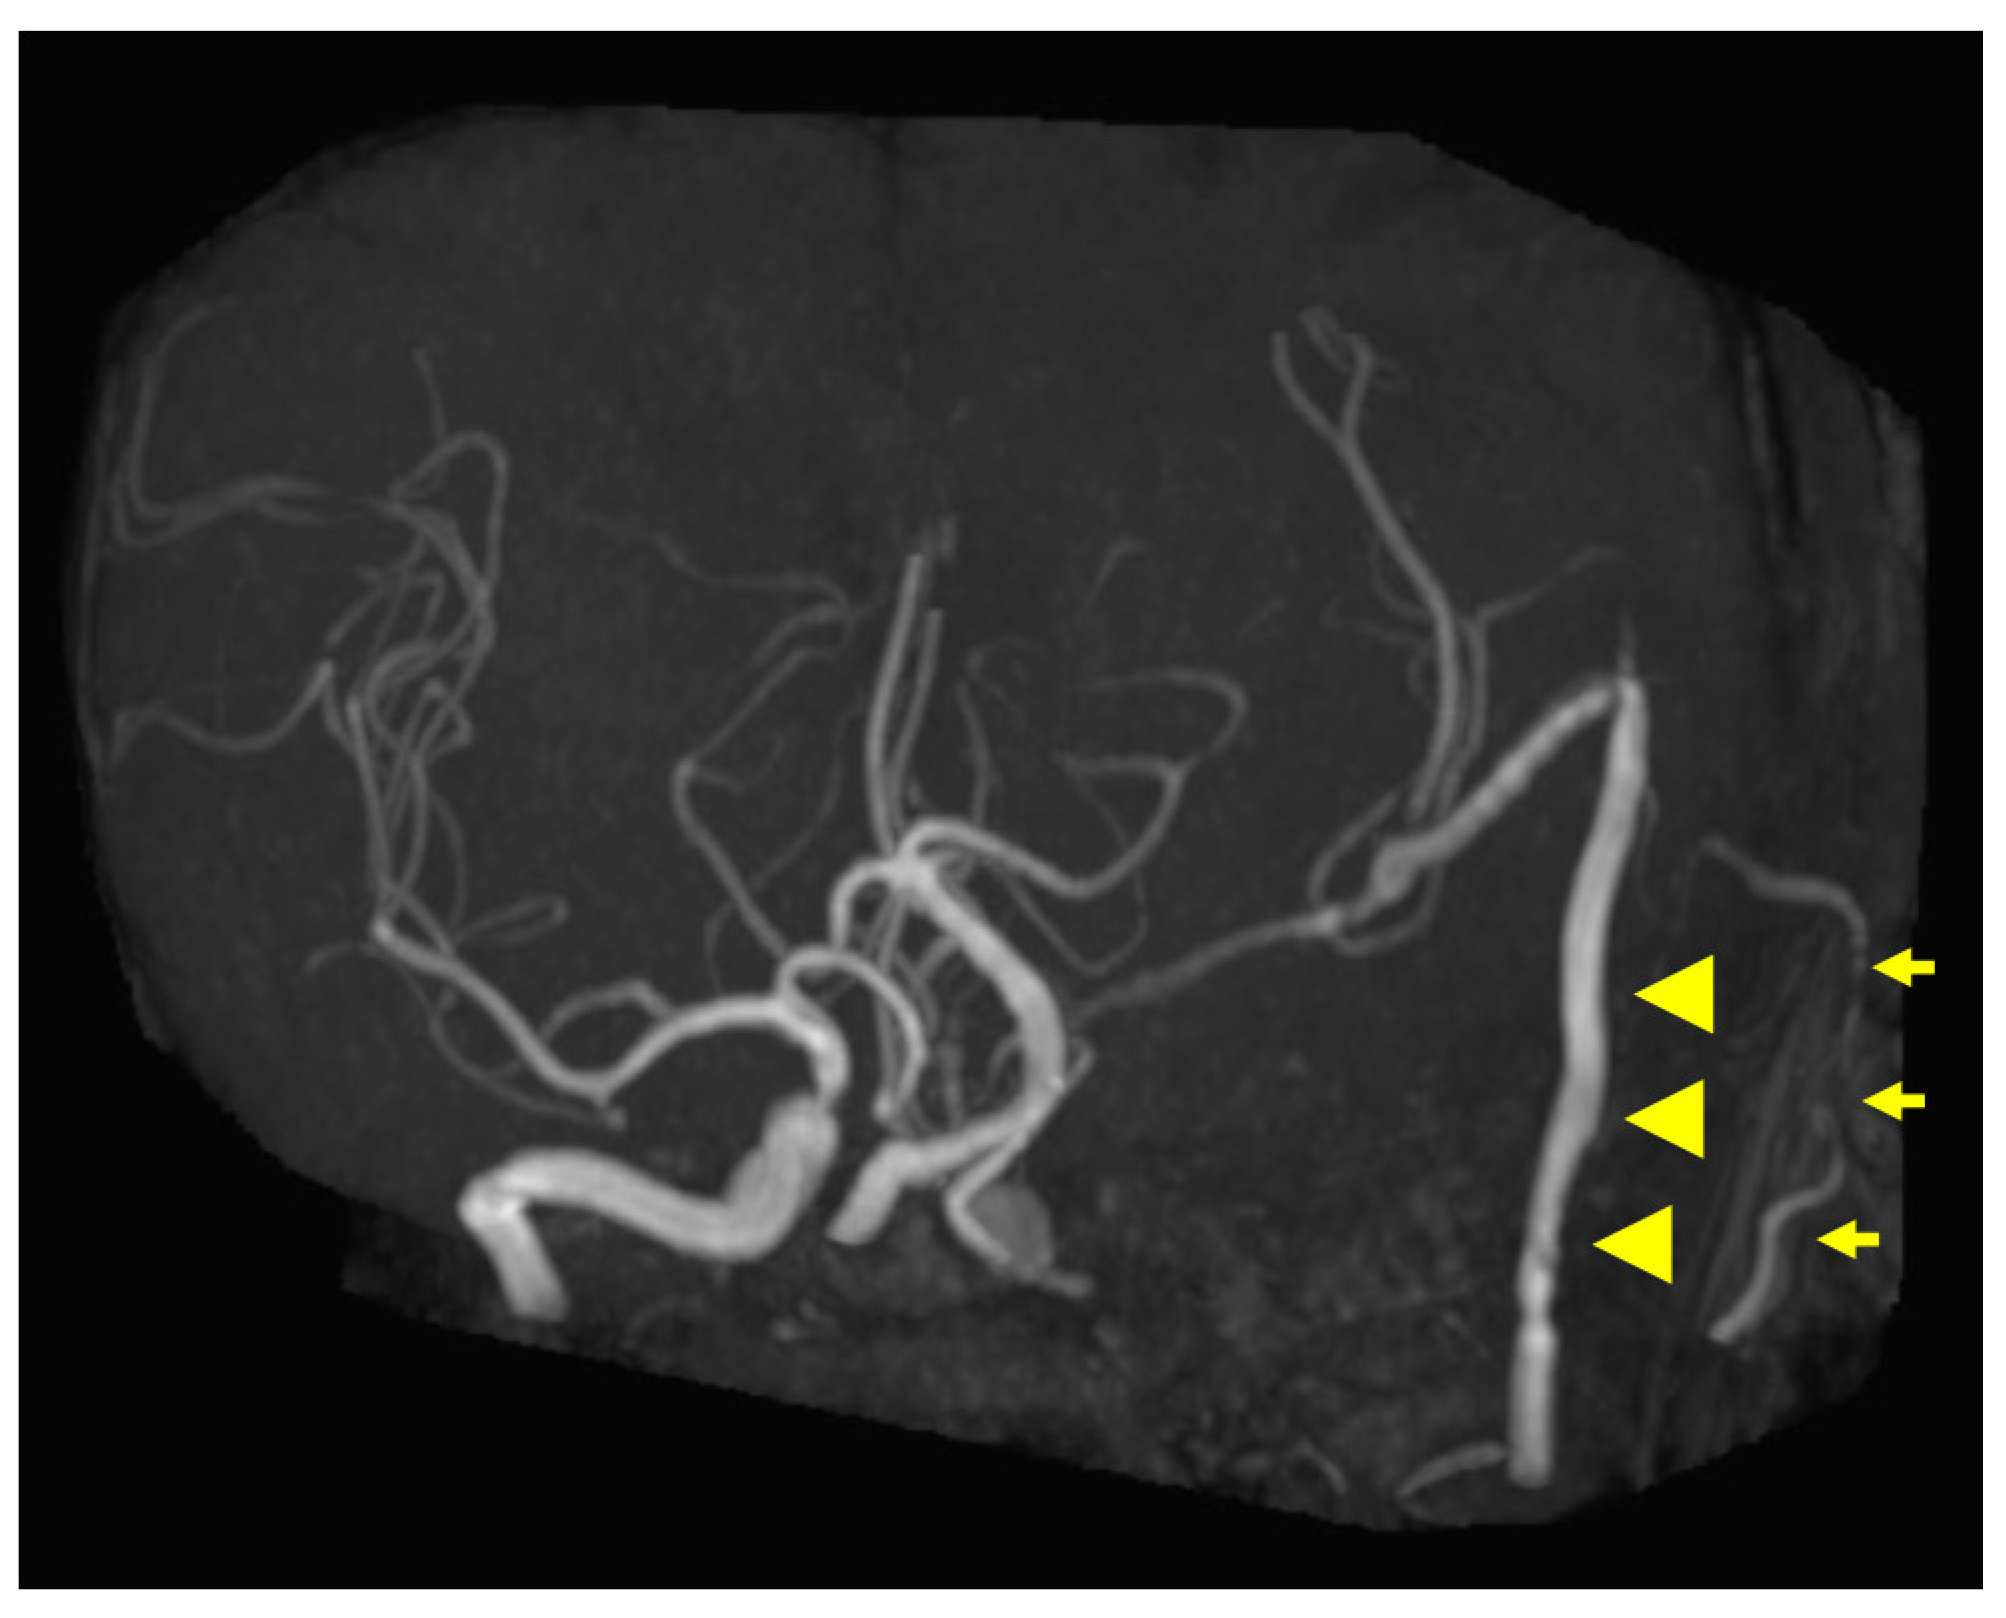

Figure 1. Preoperative contrast-enhanced computed tomography (CT) findings. Axial section (A) and coronal (B) images are shown. An isodense area with surrounding bone destruction is observed in the left sphenoid sinus, and no surrounding bone is observed around the internal carotid artery (ICA). Arrowheads indicate tumors.

A 60-year-old man without any symptoms presented to the otorhinolaryngology department with a suspected neoplastic lesion in the left sphenoid sinus, detected on magnetic resonance imaging performed during a physical examination. Imaging modalities showed that the tumor extended from the left sphenoid sinus to the area surrounding the ICA, with associated bone destruction, raising a suspicion of malignancy (Figure 1 and Figure 2). Neither regional lymph node nor distant metastases were observed. An otorhinolaryngologist performed a transnasal biopsy of the tumor under general anesthesia to determine the course of treatment. Immunohistochemical staining was positive for cluster of differentiation (CD) 56, synaptophysin, and chromogranin A. In contrast, cytokeratin AE1/AE3 staining was negative (Figure 3). Notably, there were few S-100 protein-positive cells, which are suggestive of the sustentacular cells typical of ONB. Because the diagnosis was difficult, the pathologists referred the specimens to a more specialized laboratory for additional testing. Further immunohistochemical tests were negative for both Nirenberg and Kim homeobox (NKX) 2.2 and CD99; therefore, the patient was diagnosed with olfactory neuroblastoma with Hymas pathological grade I and Kadish stage C.